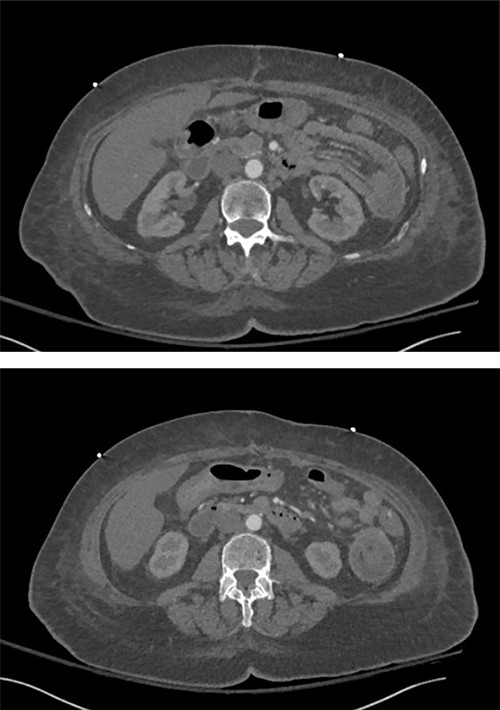

Her initial hospital course was prolonged by poor oral intake. She was ultimately discharged on postoperative day (POD) 7. On POD 8, the patient was readmitted with nausea, emesis, failure to thrive, reported syncopal episode. Laboratory studies revealed diabetic ketoacidosis (DKA). She was transferred to the surgical intensive care unit (SICU) for management of suspected DKA. On hospital Day 2, a computed tomography (CT) scan of the chest, abdomen and pelvis was ordered due to leukocytosis and hemodynamic instability requiring vasopressor use and worsening abdominal pain. Contrast was not used due to an institutional shortage of IV contrast. The scan revealed atypical pneumonia and intussusception of the proximal small bowel (Fig. 1). Lactate at that time was 3.0 mM/l. Given the concern for possible ischemic bowel and recent surgical intervention, the patient was taken back to the operating room for exploration.

Intussusception of the proximal small bowel on CT abdomen without contrast.